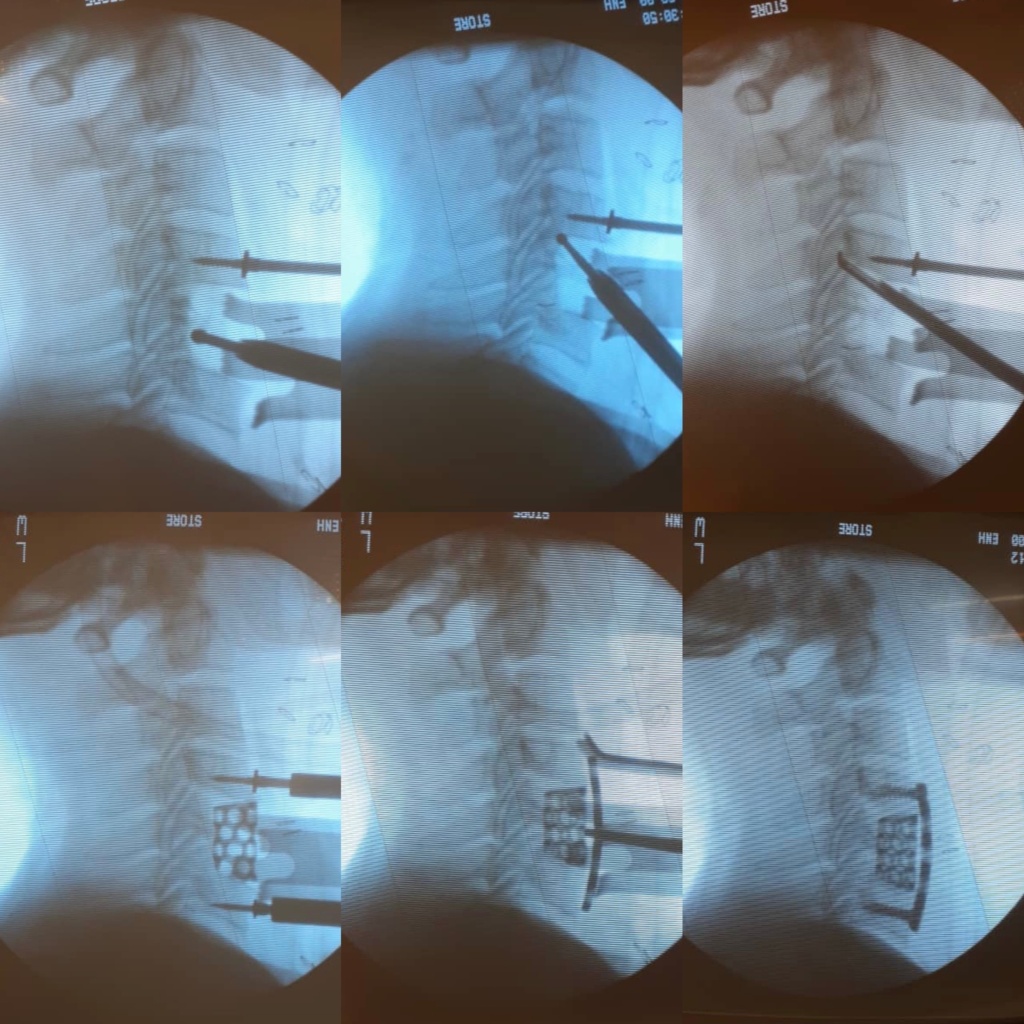

Secuencia de la cirugía.

El paciente tuvo una excelente evolución, mejorando progresivamente su destreza fina manual y su marcha alterada.